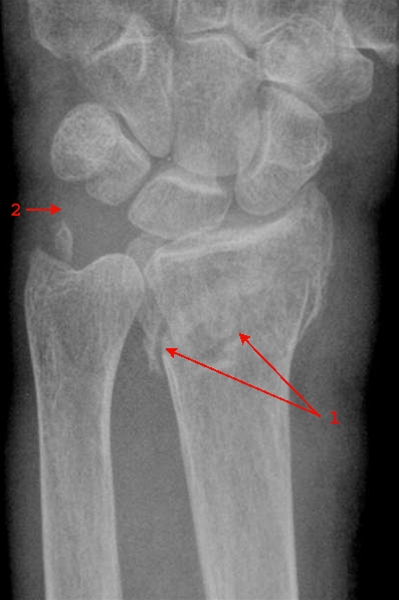

Radiusfraktur, front

Fraktur gennem distale radius (1), samt afsprængning af processus styloideus ulna (2).

Denne fraktur har dorsalvinkling af ledfladen, og kaldes også en Colles fraktur.